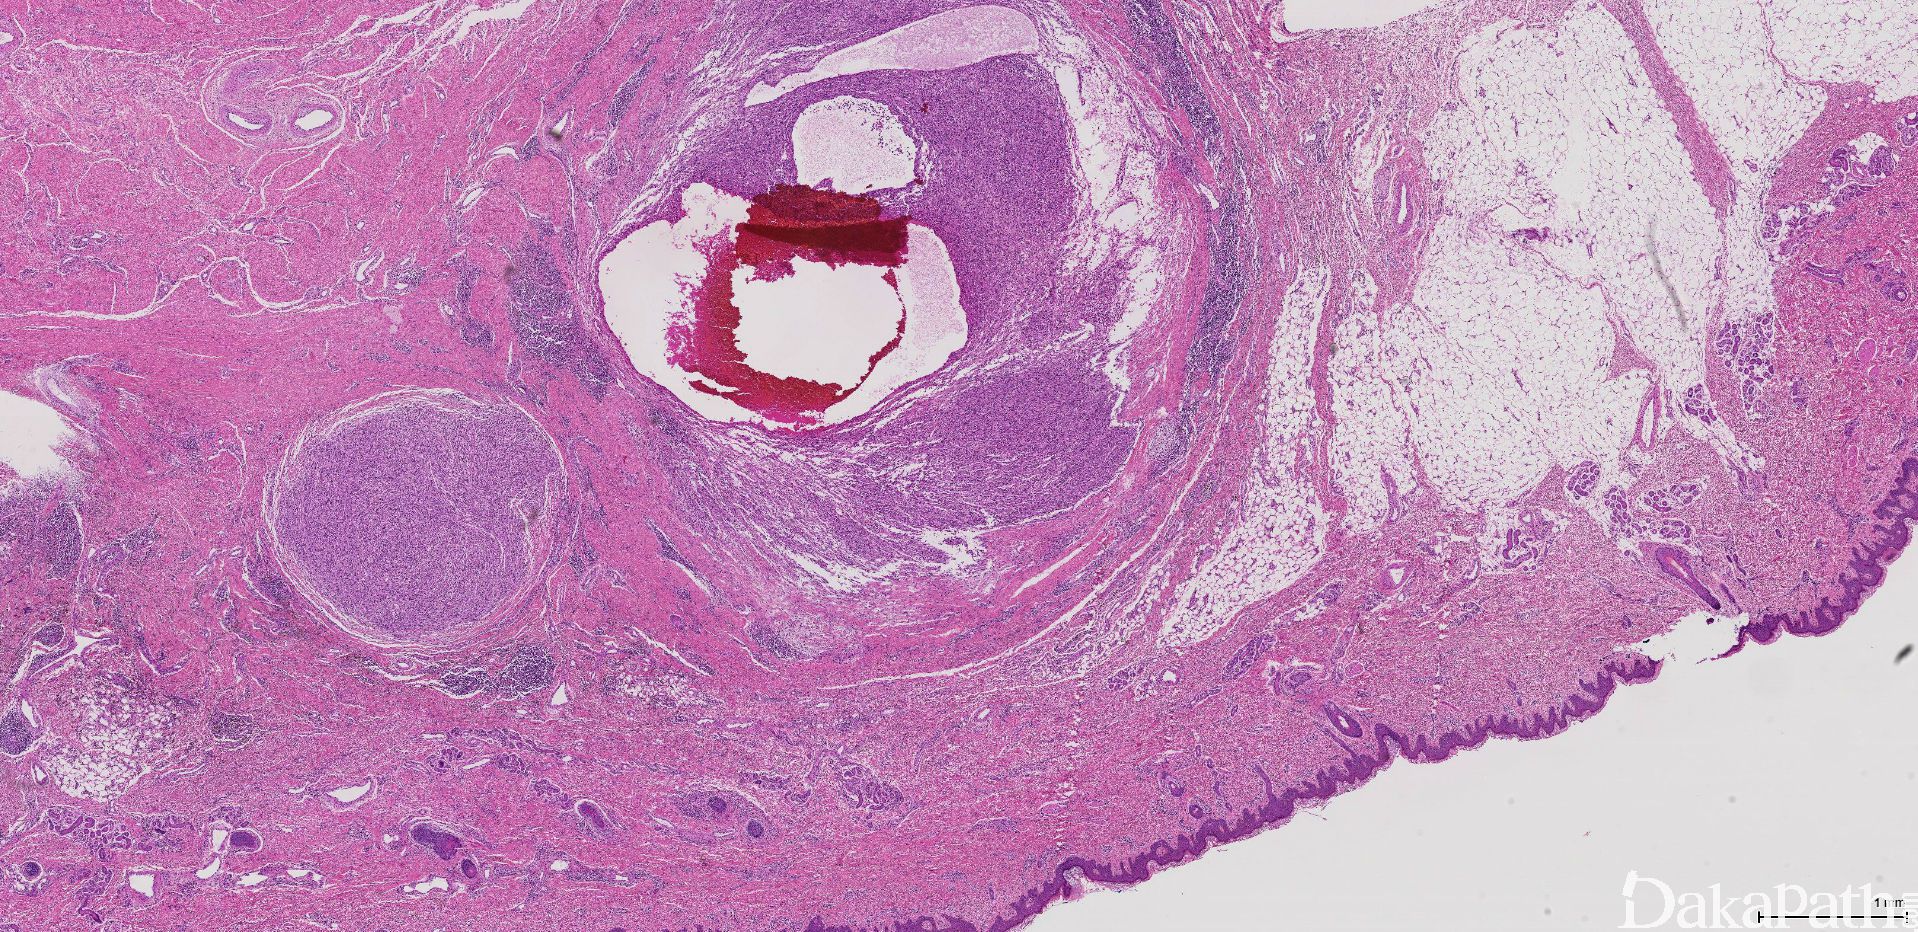

是一种好发于儿童和青少年四肢的浅表性肿瘤,主要有 4 中组织形态成分:合体细胞样梭形细胞结节伴多少不等的组织细胞、由肿瘤细胞围绕的假血管瘤样腔隙内充满血液(无内皮细胞衬覆)、厚的假纤维性包膜伴含铁血黄素沉积、包膜外淋巴浆细胞套偶伴生发中心。

主要有 4 中组织形态:合体细胞样梭形细胞结节伴多少不等的组织细胞、由肿瘤细胞围绕的假血管瘤样腔隙内充满血液(无内皮细胞衬覆)、厚的假纤维性包膜伴含铁血黄素沉积、包膜外淋巴浆细胞套偶伴生发中心。

瘤细胞巢内可见多发灶性出血性囊腔,无内皮细胞内衬,为假血管性腔隙;

肿瘤的周边可见淋巴细胞和浆细胞为主的慢性炎症细胞浸润带,偶见淋巴滤泡或生发中心形成;

炎症细胞带外可见一层较厚的纤维性假包膜,常与炎症带相融合。